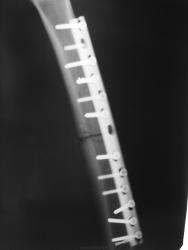

"Удачный" металлоостеосинтез.

Ирония в том, что в проекции четвёртого и последнего шурупов (счет сверху) отломки свёрел, а у второго шурупа отсутствует "шляпка". А в остальном действительно хороший остеосинтез.)))

По поводу "иронии", я не стал встревать, но иллюстрации подготовил давно, и сейчас вставлю. Я согласен с Вами по поводу "шляпки", ну конечно, количество шурупов "впечатляет", ну и поверхности линия перелома, ну прямо "зашлифованные", вопро, вот как срастаться будет.

Здравствуйте, Валентин Львович, и спасибо за иллюстрации. У меня видимо другой  графический редактор,ну нет там стрелочек((((. А посмотрите нижний шуруп,там их не два , там рядом часть сверла...